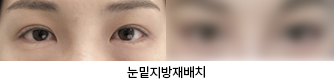

위 사진이 수술전,

아래 사진이 수술후 입니다.

위 사진이 수술전,

아래 사진이 수술후 입니다.